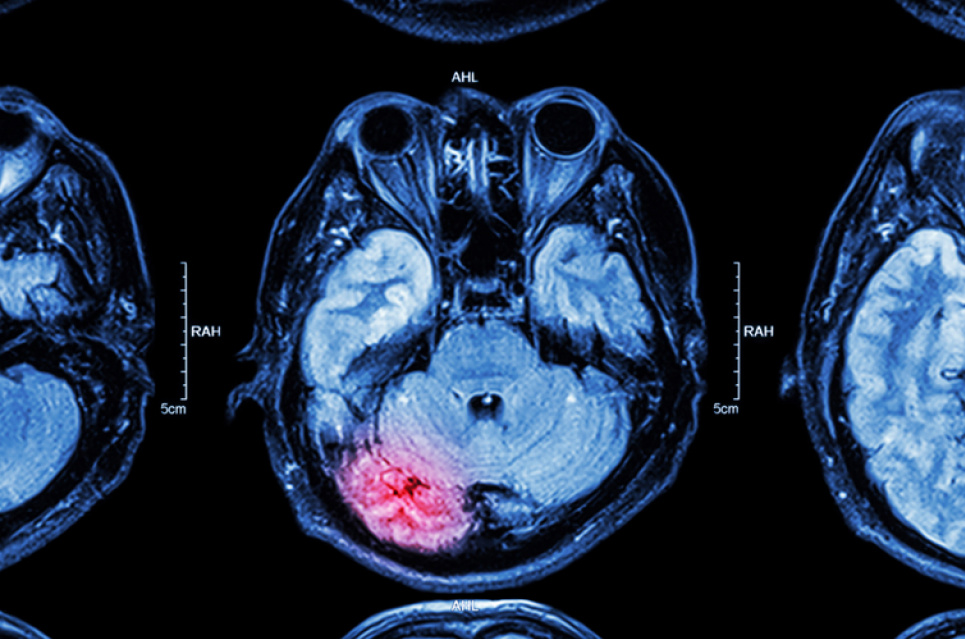

Дві щоденні звички, які підвищують ризик інсульту – чого слід позбутися у житті

Фахівці British Heart Foundation (Британський фонд Серця) назвали дві повсякденні звички, які несуть серйозні ризики пошкодження мозку та можуть спричинити інсульт. Ідеться про куріння та малорухливий спосіб життя. Про це пише еxpress.co.uk.